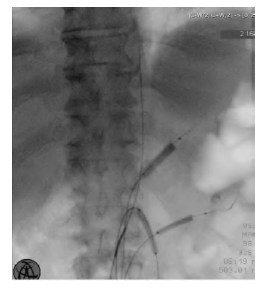

TEVAR was performed to control the embolic source and prevent further events. To minimize the risk of visceral embolization during the procedure, selective catheterization of the visceral arteries was carried out via the contralateral right common femoral artery, where a 12Fr sheath was placed. Low-pressure angioplasty balloons were inflated in the visceral arteries, including the celiac trunk, superior mesenteric artery, and left renal artery, Figure 2. The left renal artery was selected due to its better appearance when compared to the right. The thrombi were successfully excluded using a Valiant® stent graft (30x150mm), with a 20% oversize relative to the native aortic diameter. Subsequently, a left transfemoral thrombectomy was performed, achieving normal blood flow to the foot.

Low-pressure angioplasty balloons are seen inflated in the celiac trunk, superior mesenteric artery, and left renal artery, prior to stent graft deployment